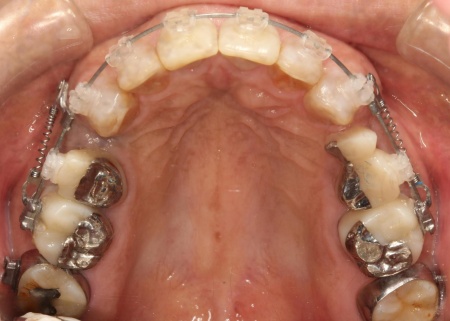

矯正期間終了後は、被せ物による治療に移行します。

上顎の前歯2本ずつと奥歯4本(左右中切歯・第2小臼歯・第1大臼歯)、下顎の奥歯7本(左第1小臼歯・左右第2小臼歯・第1大臼歯・第2大臼歯)には、見た目が自然なセラミックの被せ物「ジルコニアクラウン」を装着しました。

ジルコニアは、金属を使わないため金属アレルギーの心配が少ない点、人工ダイヤモンドと呼ばれるほどの強度をもち噛む力の強い奥歯にも適している点がメリットです。

加えて、上前歯4本(左右側切歯・犬歯)と下前歯5本(左右中切歯・側切歯・右下犬歯)は、ダイレクトクラウンによる修復を行いました。

ダイレクトクラウンとは、レジン(樹脂)を用いて直接歯の形を作り上げていく治療方法です。

歯を削る量が少ない、色や形を細かく調整しながら仕上げられる、治療後は必要に応じて微調整がしやすいなどのメリットがあります。